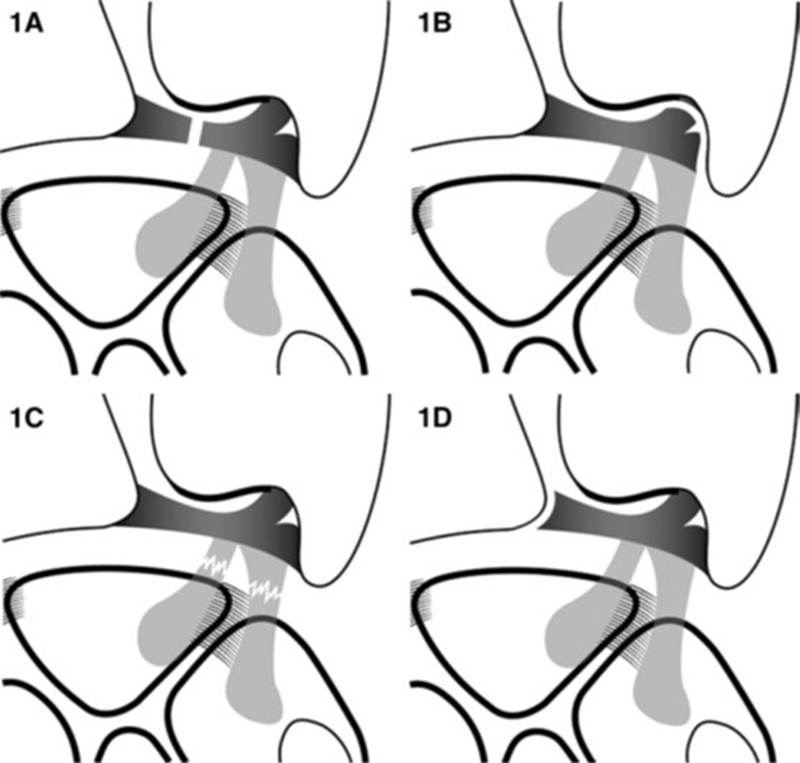

TFCC损伤分类(Palmer分类)

Ⅰ类:创伤性损伤

A:中心穿孔

B:尺侧撕裂(伴尺骨茎突骨折/不伴尺骨茎突骨折)

C:远端撕裂

D:桡侧撕裂

Ⅱ类:退变性损伤

A:TFC磨损

B:TFC磨损+月/尺骨头软骨软化

C:TFC穿孔+月/尺骨头软骨软化

D:TFC穿孔+月/尺骨头软骨软化+月三角韧带撕裂

E:TFC穿孔+月/尺骨头软骨软化+月三角韧带撕裂+尺腕关节炎